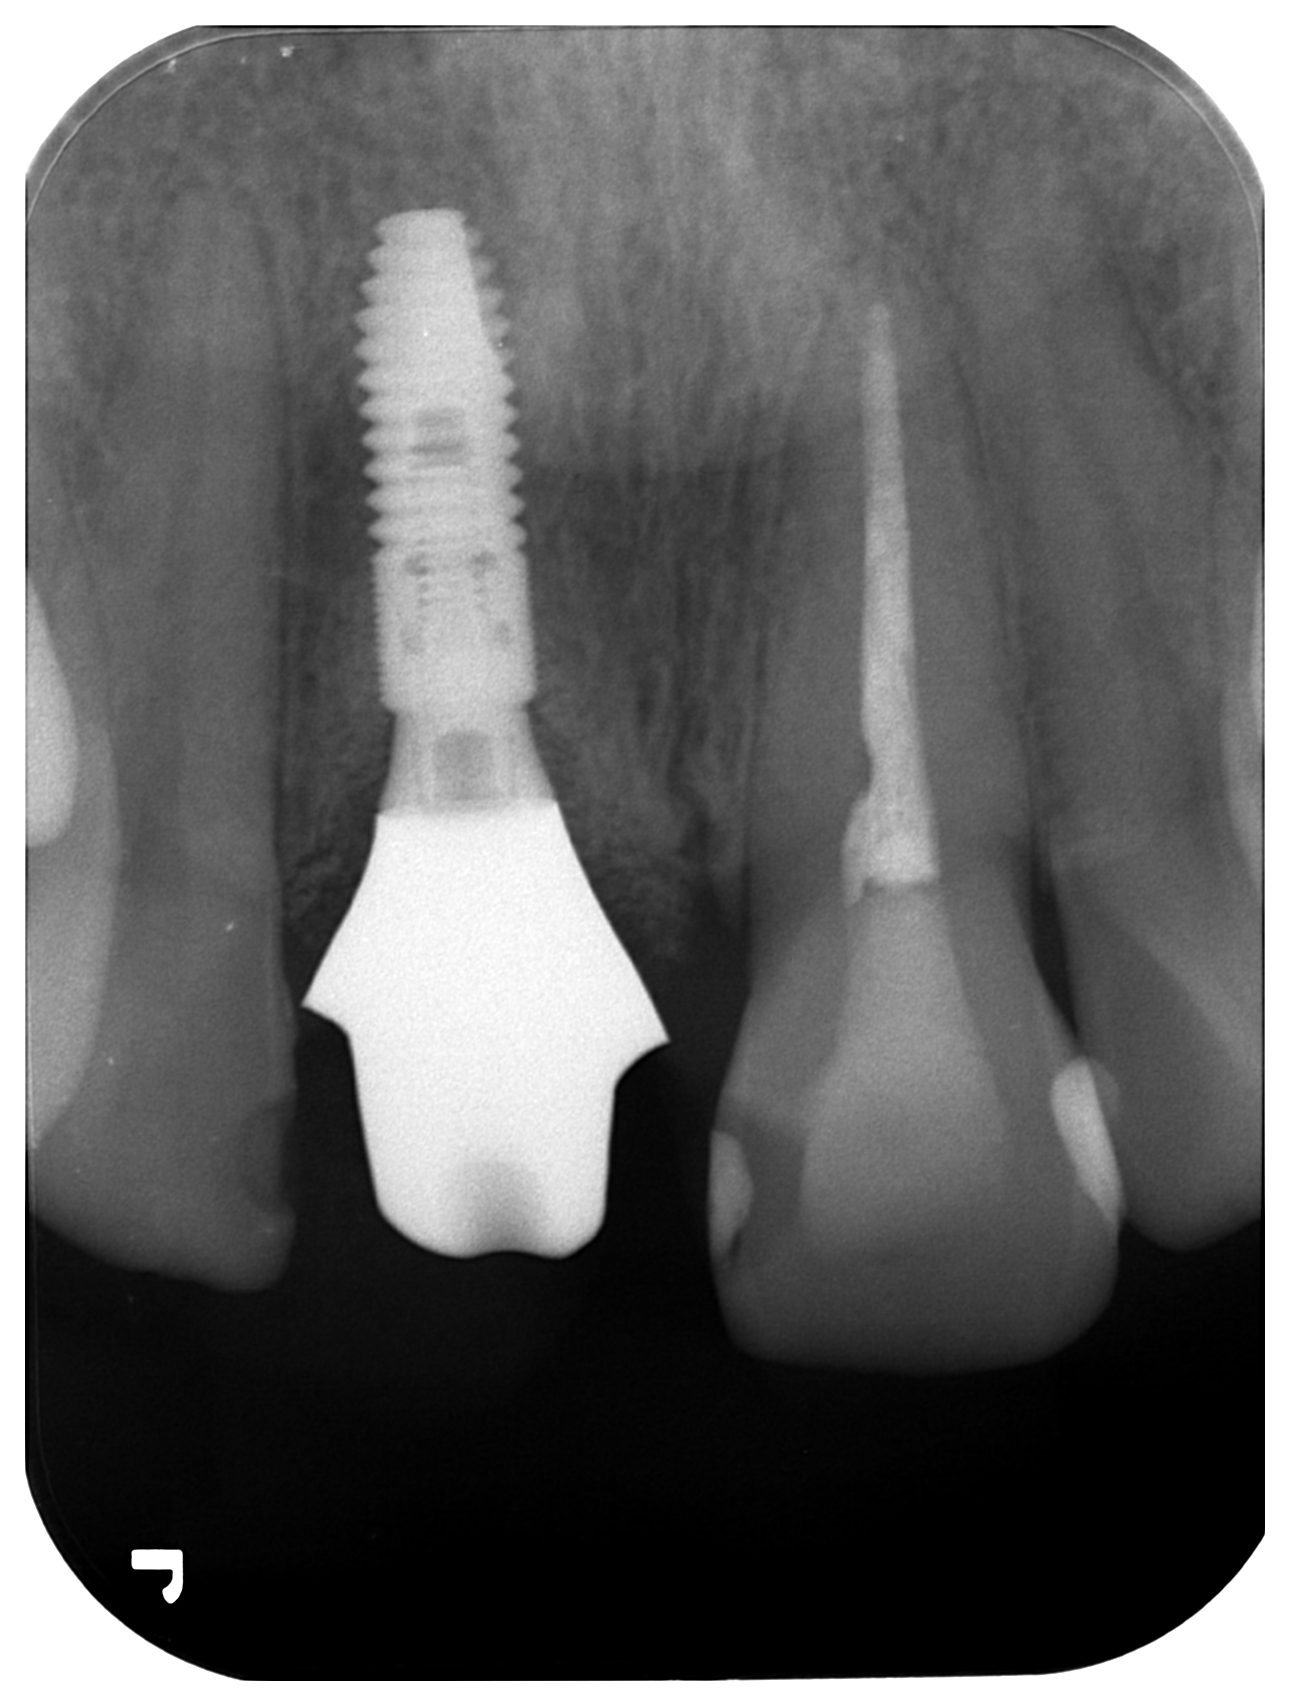

case12 症例(抜歯後待時埋入)

治療前

治療中

治療後

| 治療期間 | 12ヵ月 |

|---|---|

| 治療費用 | 870,000円(税込) インプラント2本+ポンティック、検査料、手術料、上部構造全て込みの費用です。 |

| メリット | 天然歯を削らなくて良い |

| デメリット | 骨を削る、歯肉移植が必要 |